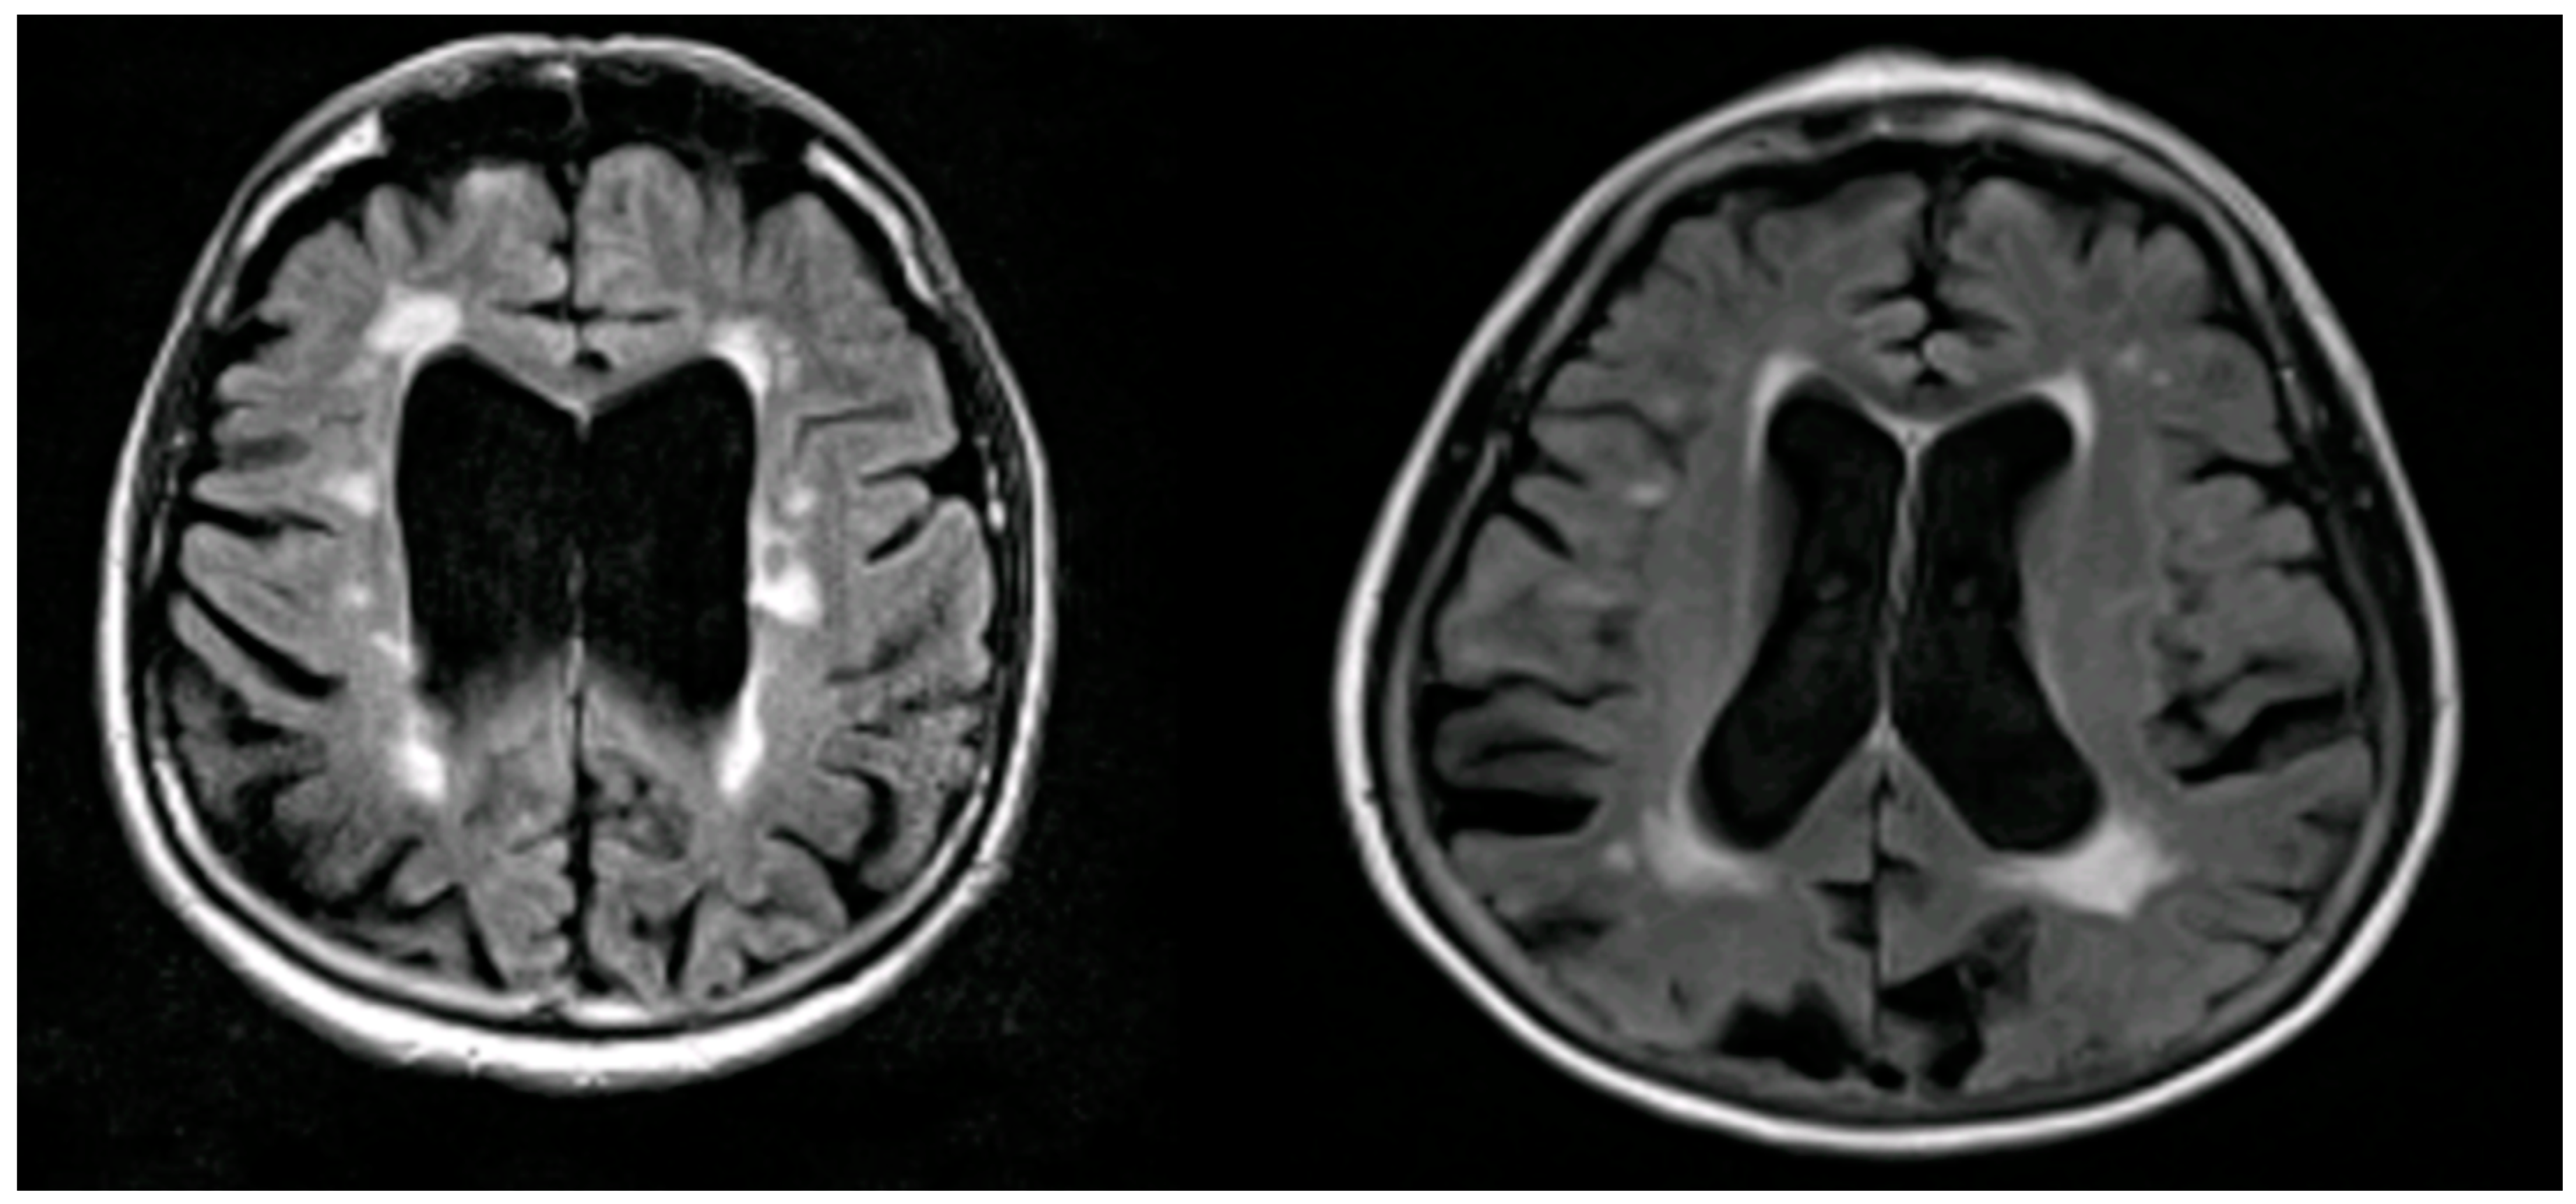

Structural Biomarkers

MRI Biomarkers in AD